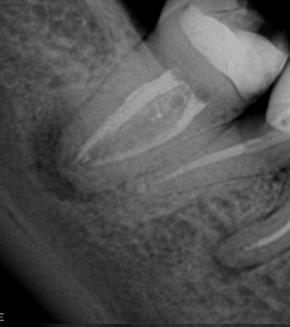

Cirujano Dentista

Prof. Dra. Patricia Ferrari

07/2018

Femenino

44 años

Periodontitis Apical asintomática. Desobturación, Preparación Químico-Mecánica, Sistemas de limpieza definitiva, Terapia Fotodinámica antimicrobiana (aPDT) y Medicación Intraconducto. 10/2018

P. O. 9 meses

P.